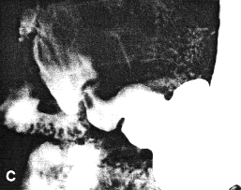

Case 29.2 I.H., 59 year old male, presented with longstanding epigastric pain and malaena. Radiographic examination showed a large ulcer in the posterior wall of the midcorpus. Endoscopic biopsy confirmed the ulcer; the gastric mucosa showed intestinal metaplasia with prominent acute and chronic inflammatory cells, diagnosed as subacute gastritis. No evidence of malignancy was found. After anti-ulcer therapy the patient was temporarily lost to follow-up, but reappeared three years later. Radiographic examination showed the following: after the first two mouthfuls of barium a large ulcer on the posterior wall of the corpus was evident as before (Fig. 29.2A). Before barium entered the duodenum a constant, deep spastic incisura was seen in the pyloric region of the distal greater curvature; swallowing more barium showed it to be due to contraction of the left pyloric loop (Fig. 29.2B). The pyloric sphincteric cylinder between the left loop and the pyloric aperture remained partially contracted, normal cyclical contraction and relaxation being absent. The pyloric aperture remained patent and emptying of fluid barium appeared normal; the appearances were unchanged throughout the examination.

Further treatment followed. Radiographic examination 18 months later showed the ulcer, the prominent contraction of the left pyloric loop and contraction of the remainder of the cylinder to be unchanged (Fig. 29.2C). Endoscopic biopsy confirmed the previous findings. Radiographic examination and endoscopic biopsy after another 5 years showed no change. Billroth II partial gastrectomy confirmed the presence of a large, chronic, benign gastric ulcer on the posterior wall of the corpus; it had penetrated into the pancreas. No organic lesion was seen or felt in the pyloric region.

| Fig. 29.2 A,B. A Case I.H. Large gastric ulcer posterior wall of corpus (open arrow). Deep spastic incisura distal greater curvature (curved arrow). B Case I.H. The spastic incisura is caused by constant contraction of the left pyloric loop (curved arrow). | |

| Fig. 29.2 C-F Case I.H. Eighteen months later the gastric ulcer (open arrow), contraction of the left pyloric loop (curved arrow) and contraction of the sphincteric cylinder are unchanged | |